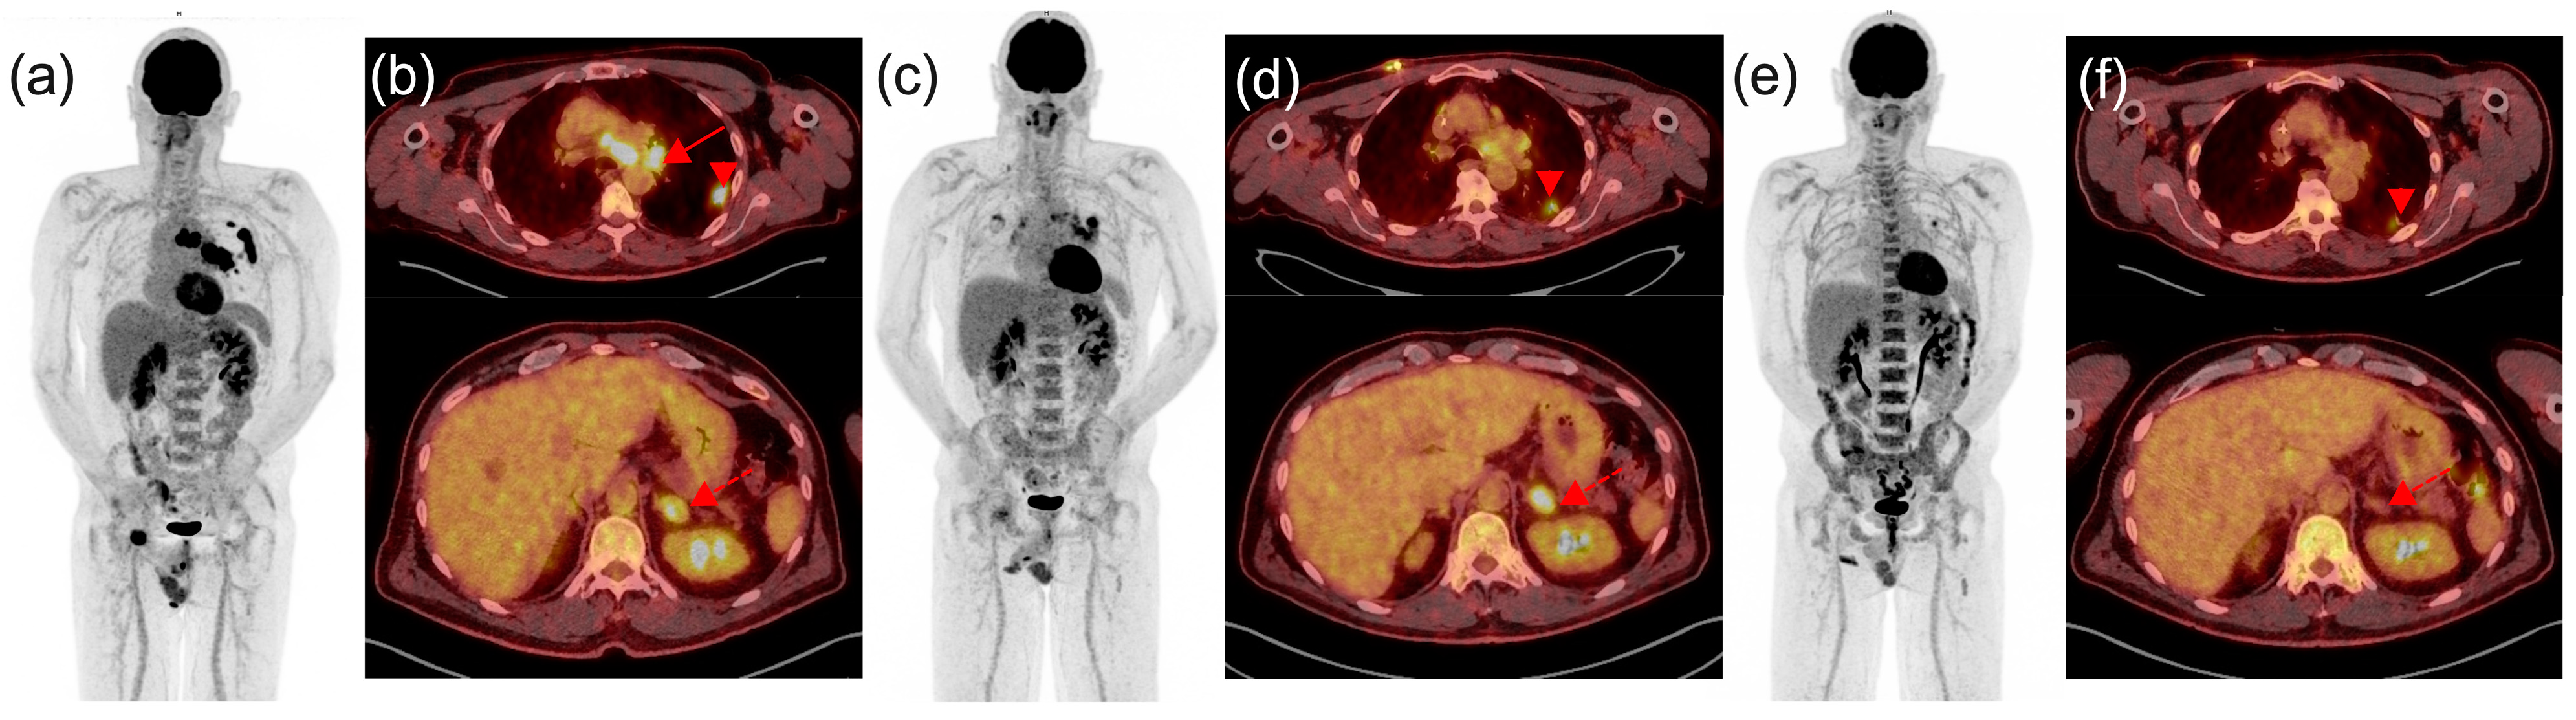

- During the treatment course, interim [18F]FDG PET/CT scans are advised, typically scheduled 8–12 weeks (i.e., 3–4 cycles) after treatment initiation [13]. This is particularly valuable for complementing information obtained from morphological imaging with CT and resolving discordant findings. Differentiating between disease progression and pseudoprogression necessitates a follow-up scan 4–8 weeks later under conditions of clinical stability, underscoring the importance of transparent communication with the treating clinician. Alternatively, a biopsy of the radiographically/metabolically progressive lesion may be warranted. PET/CT scans may also be conducted earlier or later during treatment in instances of clinical deterioration or suspected progression identified in contrast-enhanced CT. It can also guide in the management of dissociated response (DR). DR involves a decrease or stabilization in some tumor sites alongside an increase in others. Although DR is less common, it has been reported in up to 10% of cases treated with ICIs. From a clinical perspective, patients with dissociated response may benefit from treatment beyond progression potentially by continuing checkpoint inhibitor therapy and integrating local treatments, such as surgery, radiotherapy, or interventional radiological treatment of oligoprogressive lesions.

4.2. Insights from a Multidisciplinary Staff Meeting Real-Life Experience: Navigating in the Maze of PPD